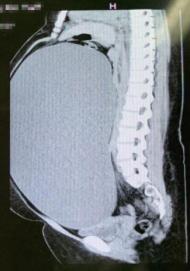

近日,15岁的少女——小朱在母亲张女士的陪同下,来到中国福利会国际和平妇幼保健院(下简称“国妇婴”)妇科肿瘤王玉东主任医师门诊处就诊,母亲张女士焦急地向医生描述起了小朱最近的反常症状。近2个月来,张女士发现女儿突然长胖了不少,但因孩子住校,她以为是饮食原因导致的肥胖,故并未在意。谁料最近,女儿的腹部逐渐隆起,还长出了很多类似“妊娠纹”的细纹,张女士顿时心急如焚,匆忙带着女儿前往当地医院进行了检查。当地医院CT检查提示:小朱盆腹腔内见一巨大液性包块,最大径达到40cm,且伴有右侧输尿管及肾盂肾盏的扩张。由于盆腔包块巨大,性质不明,当地医院一时无法制定治疗方案。张女士便带着女儿来到国妇婴就诊,期盼能够尽早得到救治。

主诊医生发现小朱的腹部明显膨隆,盆腔包块已达剑突下,且腹壁布满了“妊娠纹”,形似足月孕妇。主诊医生当即收治了该名患者,并组织妇科肿瘤联合诊治中心(MDT)行进一步检查明确,讨论治疗方案。